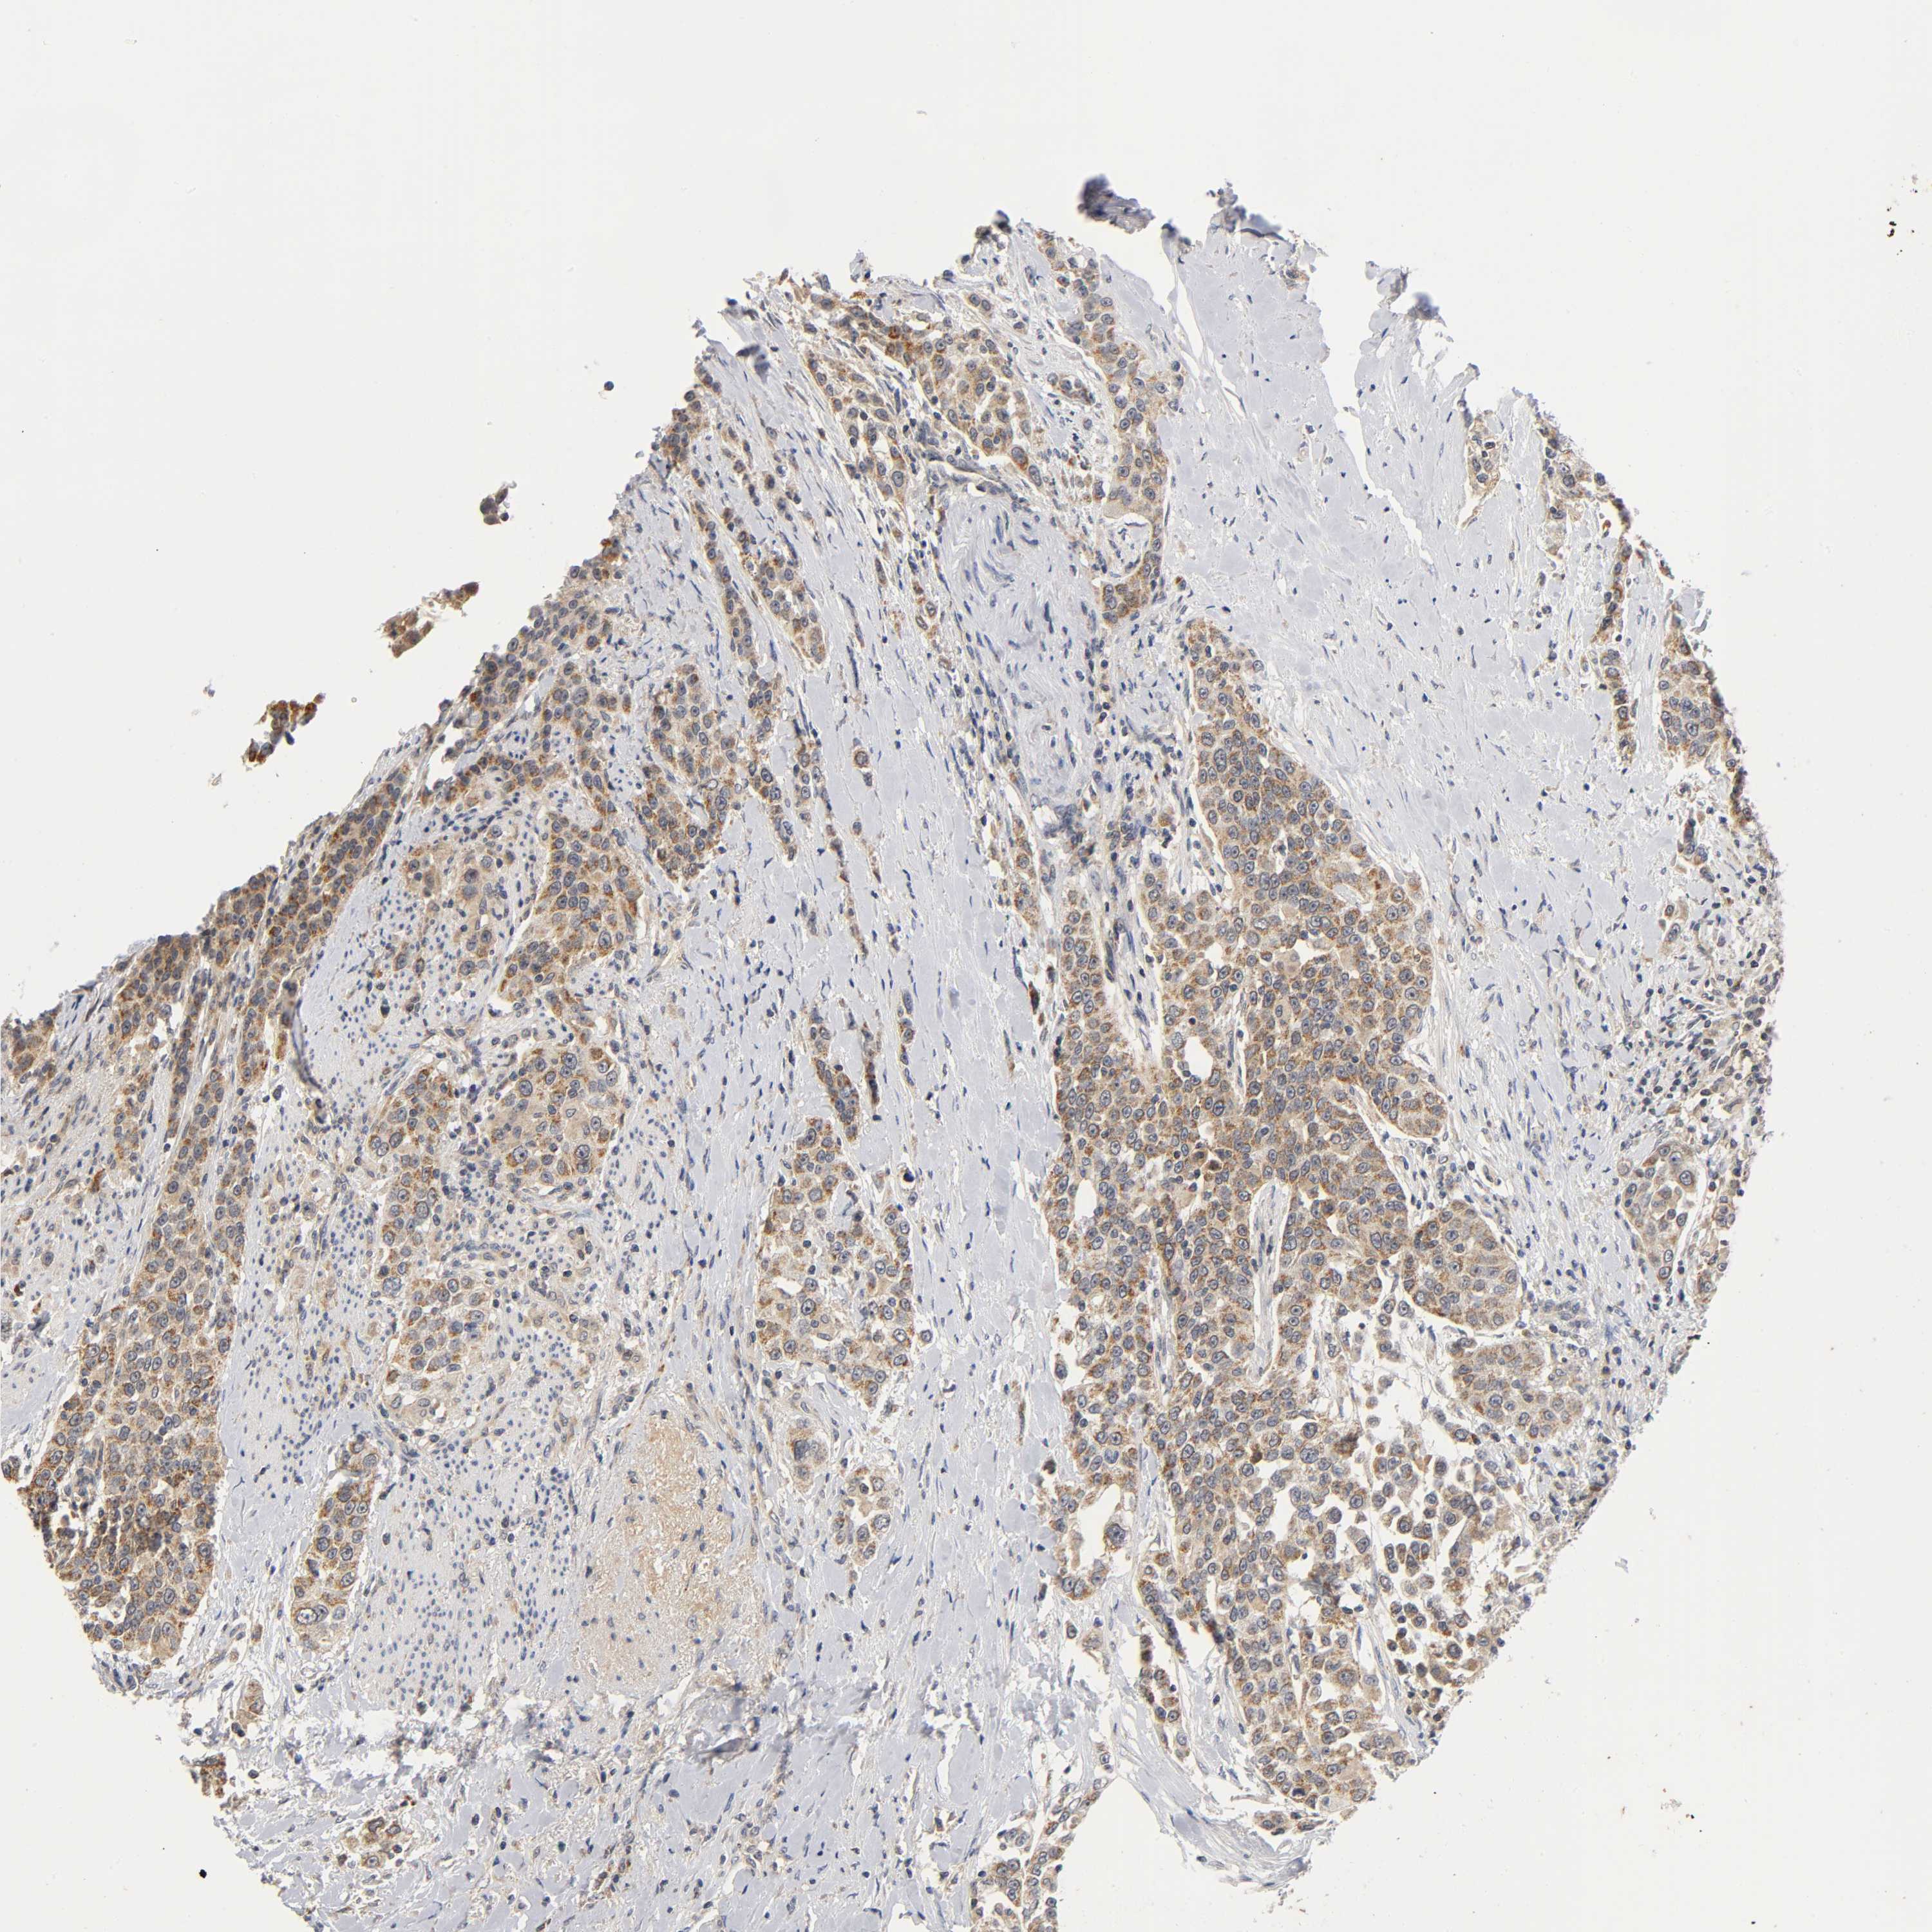

UROTHELIAL CANCER - Protein expressioni

A mouse-over function shows sample information and annotation data. Click on an image to view it in a full screen mode. Samples can be filtered based on level of antibody staining by selecting one or several of the following categories: high, medium, low and not detected. The assay and annotation is described here.

Antibody stainingi

Antibody staining in the annotated cell types in the current human tissue is reported as not detected, low, medium, or high, based on conventional immunohistochemistry profiling in selected tissues. This score is based on the combination of the staining intensity and fraction of stained cells.

Each image is clickable and will lead to virtual microscopy that enables deeper exploration of all samples and also displays staining intensity scores, fraction scores and subcellular localization as well as patient and tissue information for each sample.

Antibody HPA030278

Antibody CAB004511

Urothelial carcinoma, Low grade

Urothelial carcinoma, High grade